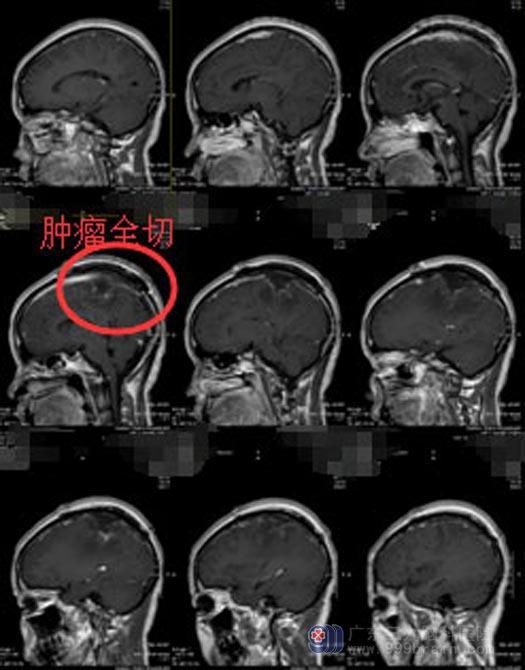

由综合神经外科鲁明主任主刀,在全麻下行“右侧顶部镰窦旁巨大占位性病变切除手术”,术中见肿瘤侵犯上矢状窦,呈灰白色,质地中,血运丰富,显微镜下全切肿瘤,上矢状窦保护完好。术后潘女士恢复良好,已康复出院。病理提示:纤维型脑膜瘤,WHO I级。

手术后